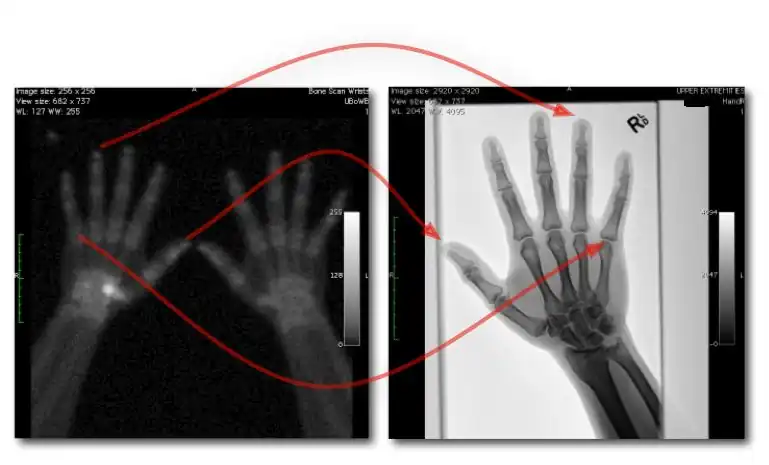

- Dual exposures: where two separate exposures are used in applications where patient movement isn't an issue; and

- Single exposure: where two imaging plates separated by a filter are mounted in a dual-energy cassette to record the low energy image on the anterior plate and the high energy image on the other.

- The form of image data processing is illustrated in Figure 7.17.